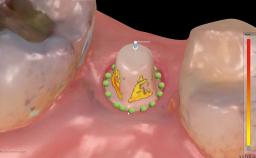

Replacement of a Mandibular Central Incisor with an Immediately Placed Monotype Zirconia Implant

In this case, immediate implant placement and an immediate provisional prosthetic reconstruction (type 1A) were performed by Stefan Röhling and Thomas Borer to reduce the treatment time and to provide the patient with a fixed implant-supported prosthetic reconstruction directly after implant placement.

| Timing of placement | Immediate Placement (extraction sockets) (Type I) |

| Available apical bone to achieve primary stability | Sufficient height ( ≥ 4 mm) and width (> 2 mm around apex of planned implant) |

| Socket walls | Intact |

| Thickness of buccal wall | 2mm or greater |

| Anticipated residual defect after implant placement | 2 mm or less |